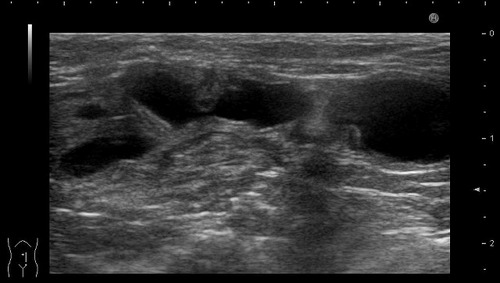

08150855.jpg

直径約8mmに腫れた子宮の異常をエコー検査で発見!(黒くなっている部分です)